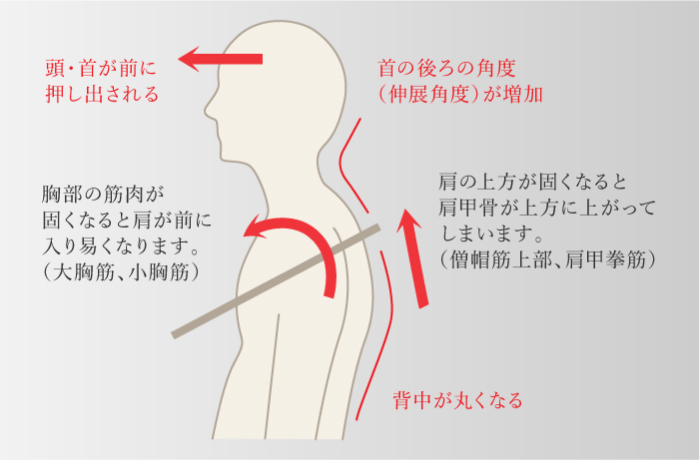

前方頭位

上位交差性症候群

前方頭位

上位交差性症候群

-

頭や肩が前に出て、背中が丸くなっている姿勢

上位交差性症候群

-

首の骨に負荷が継続的にかかり続けることで椎間板が変性し、骨棘を形成することよって、頚椎にある「椎間孔」が狭くなり、神経根が圧迫された刺激されて肩や腕の痛みや痺れといった症状をきたす。